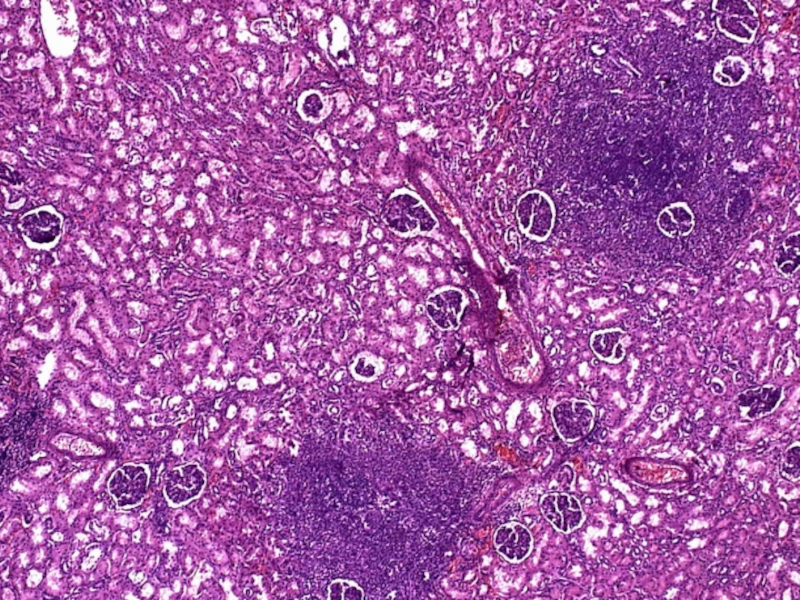

Слайд 78ТБ почки

ТБ почки